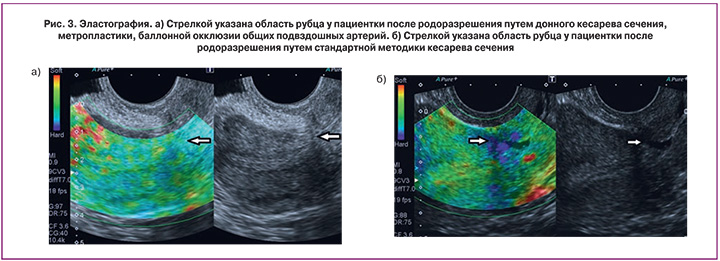

С помощью эластографии в режиме реального времени с цветовым кодированием изображения была исследована область послеоперационного рубца в обеих группах. Данная методика дает возможность определять эластические (упругие) свойства ткани в дополнение к данным об эхоструктуре. Синим цветом на изображении отмечаются участки более плотные по своей структуре. При изучении эластичности тканей миометрия в области рубца получены следующие результаты: в 1-й группе в области рубца ткань по структуре очень жесткая (синий цвет) в 5 (62,5%) наблюдениях, менее жесткая (зеленый цвет) – в 2 (25%), в 1 (12,5%) наблюдении зафиксирован миометрий желтого цвета. Во 2-й группе в 5 (56%) наблюдениях миометрий в области рубца желтого цвета, в 2 (22%) – зеленого, в 2 (22%) наблюдениях – красного цвета. Преобладание красного и желтого цвета свидетельствует о наличии более эластичной ткани в зоне исследования (рис. 3а). Наличие синего и зеленого цвета свидетельствует о повышенной жесткости в области рубца (рис. 3б). Отсюда следует, что у этих пациенток в зоне исследования повышено содержание соединительной ткани, а не мышечной, что в дальнейшем может привести к несостоятельности рубца. Полученные данные объединены в табл. 3.

Данные приведенные в таблице показывают, что процесс формирования рубца у пациенток, перенесших донное кесарево сечение, происходит с преобладанием эластичных мышечных волокон.